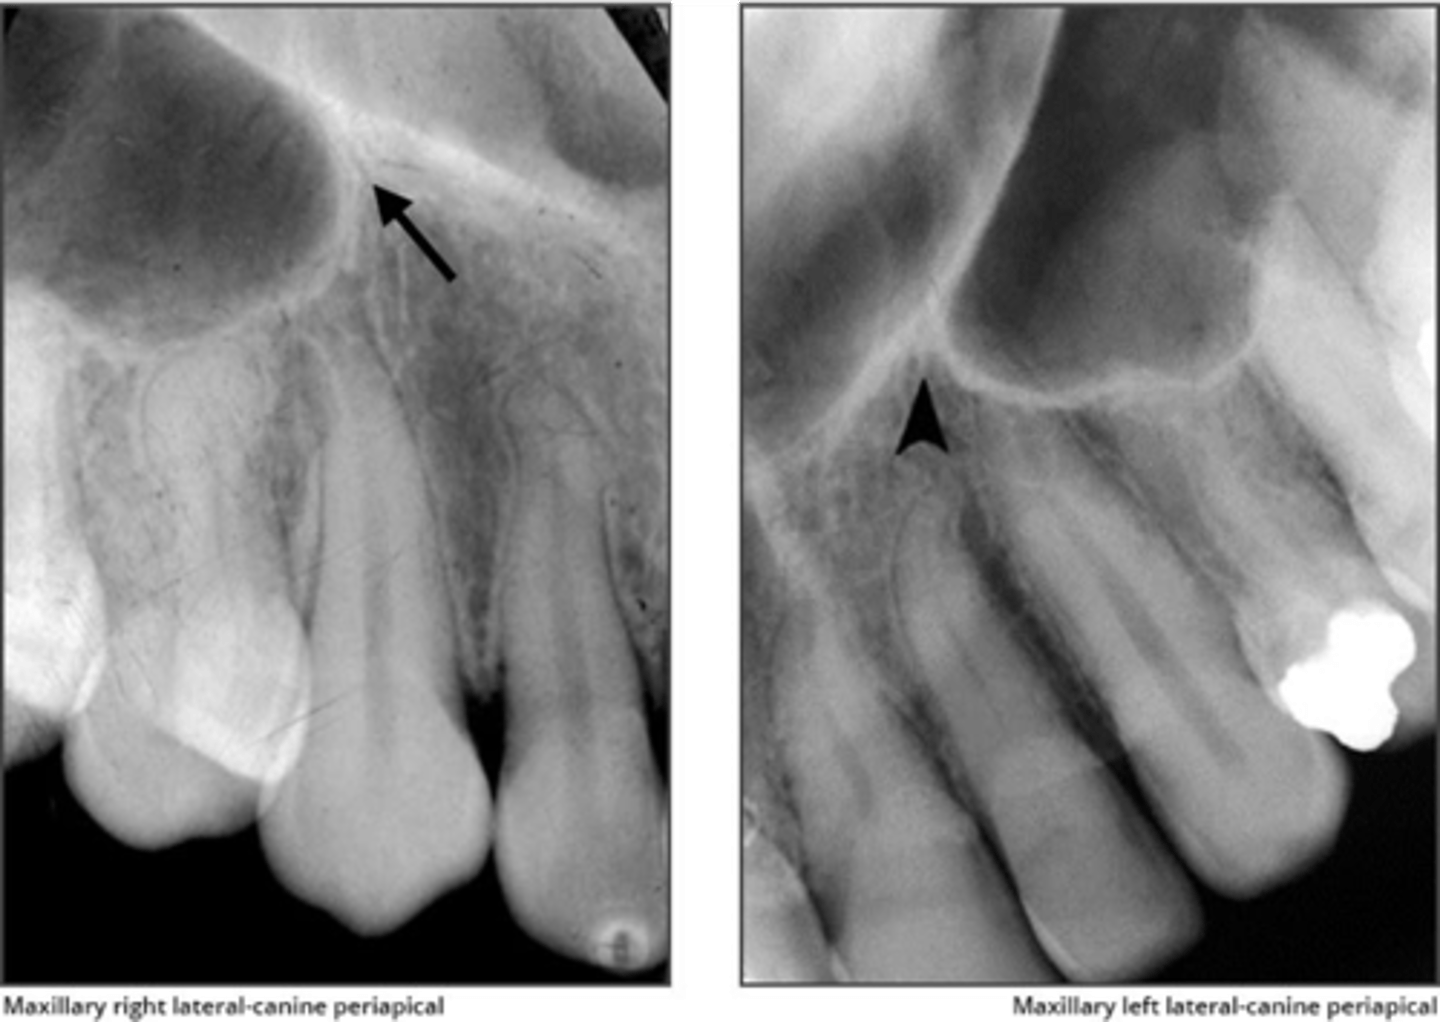

Zygomatic process

What is the radiopaque structure seen in the upper right picture?